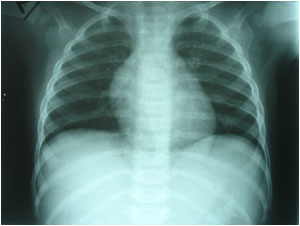

Normal CXR |

Normal CXR

برداری از جمله

CXRay-Abdominal

XRay - VCUG

نرمال

بودند.